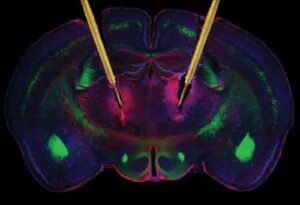

Il team ha usato una tecnica sviluppata nei topi che permette loro di mettere insieme informazioni sulla funzione dei neuroni e i dettagli delle loro connessioni sinattiche. Usando imaging ad alta risoluzione all’interno della corteccia visiva del cervello del topo, che contiene migliaia di neuroni e milioni di diverse connessioni, il team è riuscito a rilevare quali di questi neuroni rispondeva a un particolare stimolo, per esempio una superficie orizzontale.

I ricercatori hanno poi studiato un altro sottogruppo di neuroni per vedere quali neuroni rispondevano allo stesso stimolo; questo ha permesso loro di stabilire se questi neuroni erano sinatticamente connessi al primo gruppo di neuroni.

Hanno scoperto che i neuroni che rispondevano in maniera molto simile allo stesso stimolo visivo, come superfici con la stessa orientazione (cioè una superficie orizzontale o una superficie verticale) o a caratteristiche visive più complesse come visi, tendevano a connettersi di più tra di loro rispetto a quelli che rispondevano a stimoli diversi.